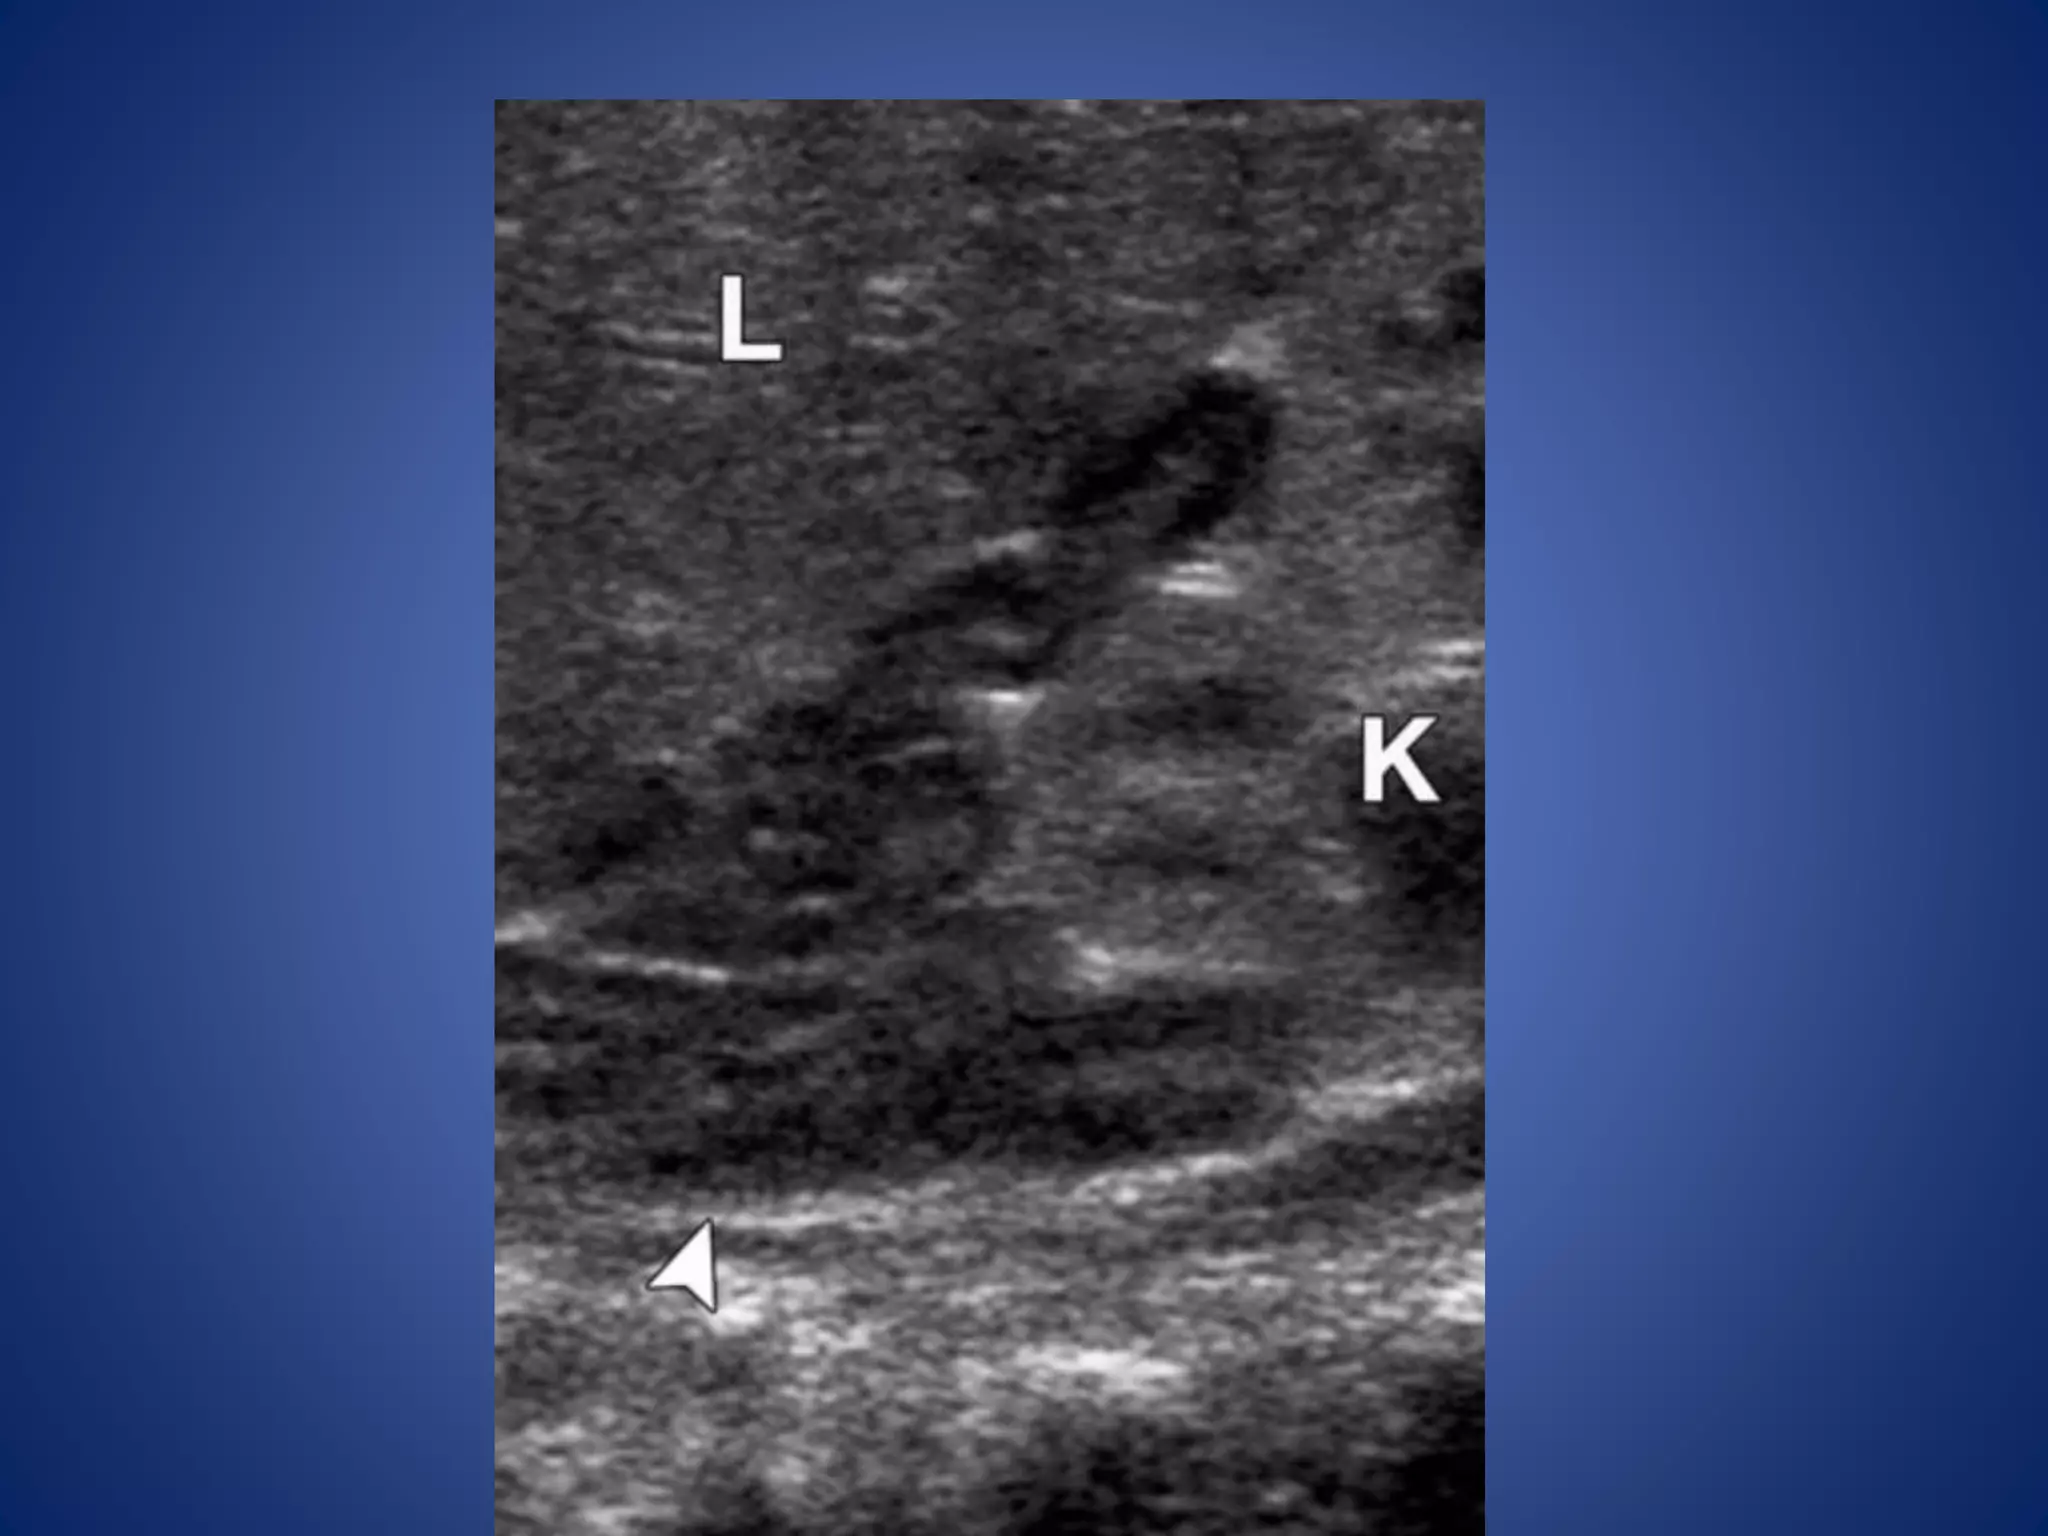

At US, smallerlesions are generally homogeneously hypo- or hyperechoic. Larger lesions may have a more heterogeneous nodular appearance or may contain central or diffuse hypoechoic areas corresponding to necrosis. The mass may be surrounded by a hyperechoic, capsule-like rim. Use of color Doppler imaging is helpful in evaluating for caval extension of tumor

• #42 ACN in a 23-month-old girl with virilization. (a) Longitudinal US image shows a large, lobulated adrenal mass (arrows) above the kidney